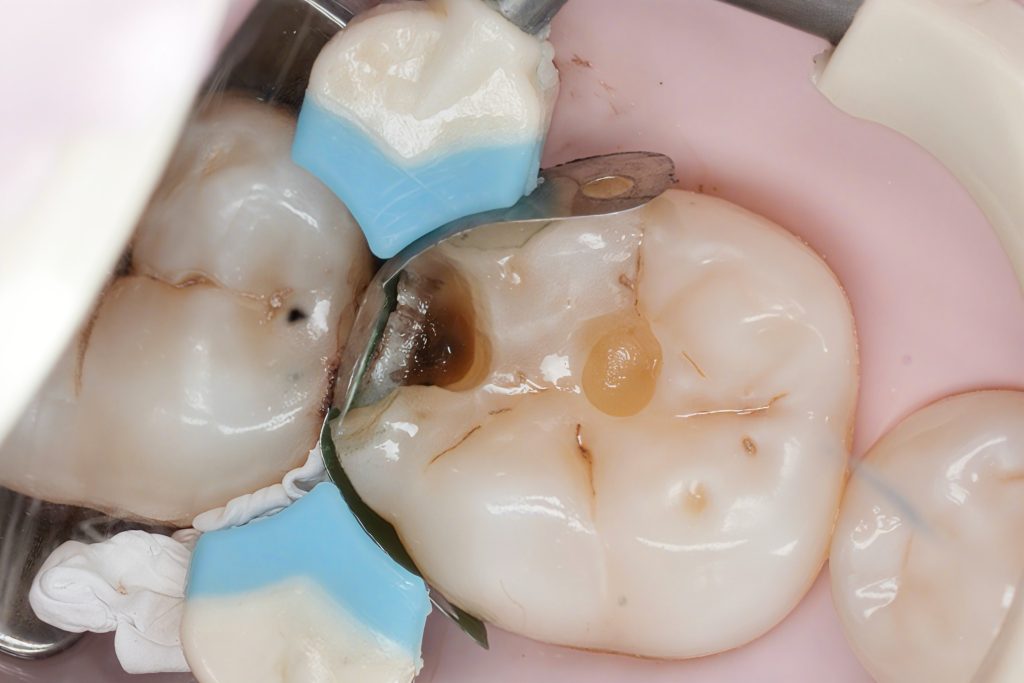

4.2 Caries Removal

The old stained fissures and proximal lesion were accessed minimally.

Dark, demineralized dentin was removed carefully with controlled speed burs. The deepest dentin was preserved following selective caries removal to avoid unnecessary pulp stress.

You can clearly see in the photos:

- clean peripheral enamel

- sound dentin base

- a defined proximal box ready for matrix placement

4.3 Matrix Placement & Contact Formation

A sectional matrix with a wooden wedge and separation ring was used.

The key elements:

- matrix positioned flush with the gingival margin

- firm wedge to seal the cervical gap

- ring for slight tooth separation

- ensuring a slight convexity cervically to mimic natural emergence

This combination created the space needed to form a tight, anatomical contact.